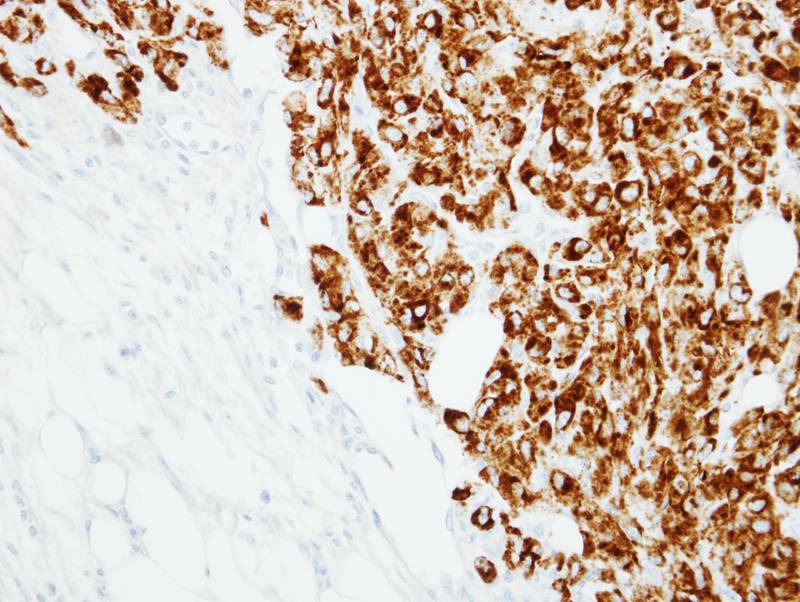

Immunohistochemical analysis of paraffin-embedded U87 xenograft, using RANKL antibody at 1: 100 dilution.